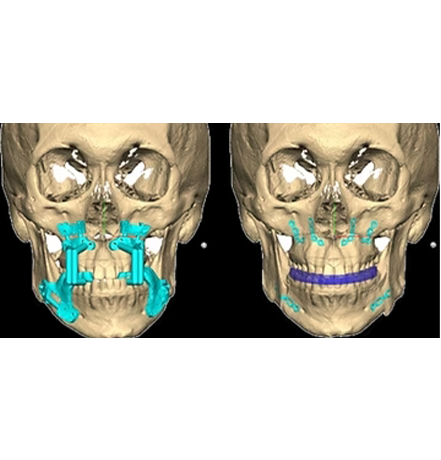

상악과 하악을 절골합니다.

절골된 상악과 하악을

수술 계획에 맞게 이동하여

교합을 맞춥니다.

절골된 뼈를 단단히 고정해

움직이지 않도록 하여,

올바른 교합과 조화로운 얼굴로 완성합니다.

서울페이스21은 고성능 3D 진단 시스템과 3D 모의 수술 프로그램을 활용하여,

수술 전 정밀한 분석부터 수술 과정, 그리고 수술 후 예상되는 얼굴형 변화까지 체계적으로 시뮬레이션합니다.

이를 통해 환자 개개인의 골격 구조와 특성을 반영한 맞춤형 수술 계획을 수립하여 보다 정교한 수술을 제공합니다.